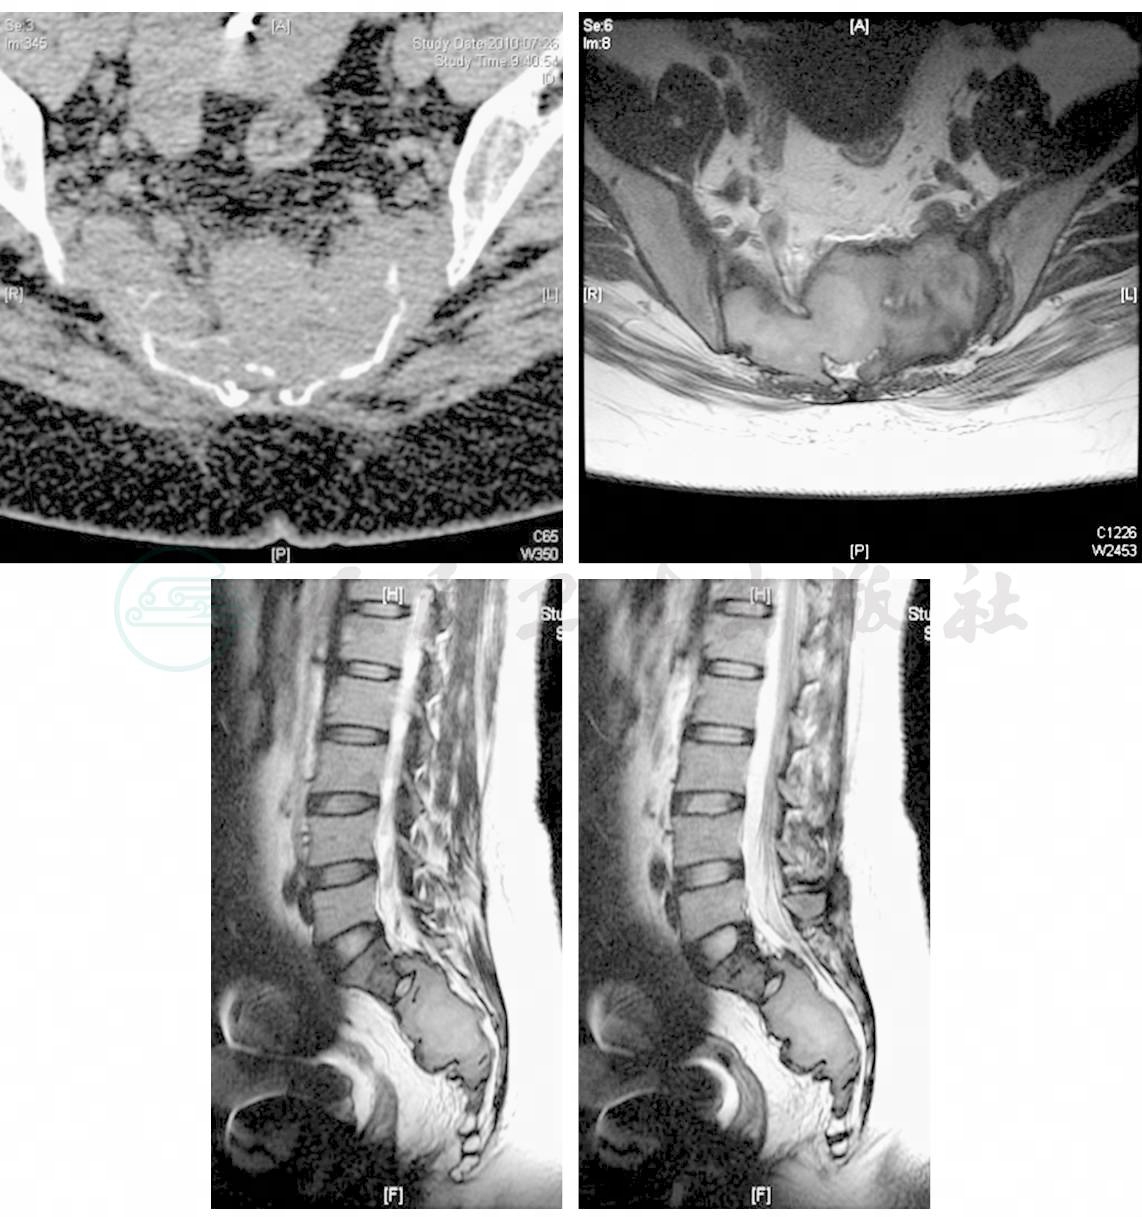

女性,27岁,因“腰背痛半年,加重伴左下肢疼痛2天”入院。患者自述,半年前无明显诱因出现腰部酸胀不适,间歇性加重,无下肢放射痛,卧位翻身及行走时加重,平卧休息后略缓解。2天前症状加重,并出现左下肢放射痛。于当地医院就诊,X线片见骶骨破坏(图1),CT及MRI显示:骶骨肿瘤(图2),转来我院。患者自发病来,大小便正常。既往体健。入院查体:腰椎活动受限,四肢感觉肌力正常,上下肢肌力Ⅴ级,左膝腱反射( + + ),右膝腱反射( + ),双Babinski征(-)。

图1 X线片见骶骨破坏

图2 骶骨破坏,部分残留骨嵴